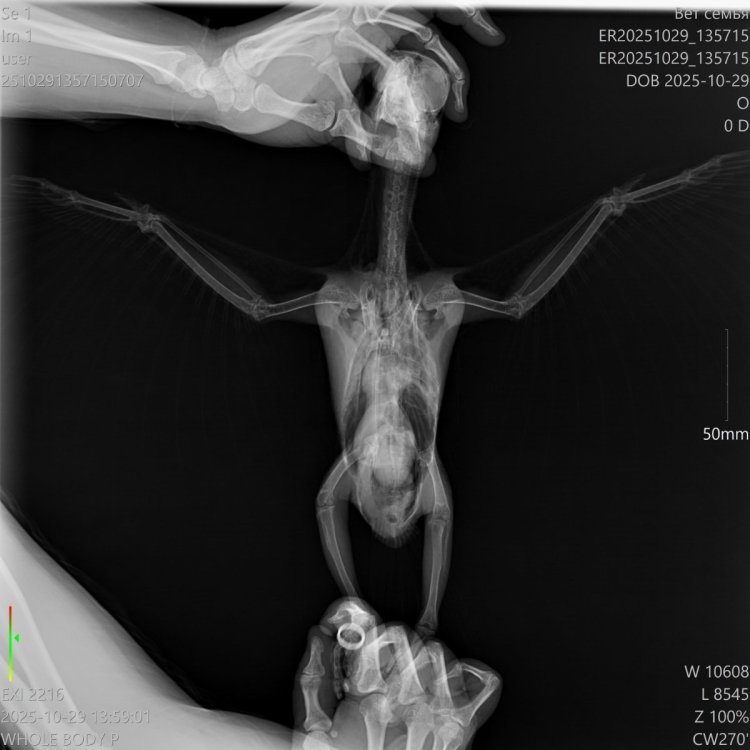

Добрый вечер!!! Ситуация такая, попугай жако 7 месяцев, внезапно заболел, перестал есть, сидит весь вжался в себя. Кормили всегда одним и темже кормом РИО, воду часто меняли, клетка убиралась часто, в доме тепло, ел фрукты и овощи каждый день. Отвезли на стационар в клинику, сделали снимки, врач кормил его через катетор, он с трудом ел, помета почти небыло и весь тресся, кололи ему антибиотики. К сожалению наша птичка вчера умерла. Хотя 3 дня назад была очень активная, играла и общалась. Помогите пожалуйста определить по снимкам что на этих снимках, есть ли какие серьезные отклонения.

ER20251029_135715_ER20251029_135715__29-10-2025 14_00_11_1-2 (1).jpg

ER20251029_135715_ER20251029_135715__29-10-2025 13_59_01_1-1.jpg